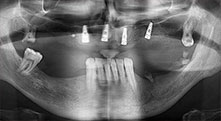

Брату: Ние предпочитаме да използваме техниката "сандвич" за аугментация в страничната долна челюст. Покритие на костта се подготвя с пиезо трион и кресталният фрагмент се фиксира с микровинтове. Поставяме смес от автогенна костна присадка и ксеногенен костозаместител между тях. Това работи много надеждно. Трябва винаги да осигурявате достатъчно оразмерени вертикални срезове при шиниране на алвеоларния гребен в долната челюст. В противен случай, костта лесно може да бъде счупена.

Вашата болница в Тимишоара предлага орална хирургия и протетично възстановяване с акцент върху имплантологията. Използвате ли Вашия апарат Piezomed за други индикации?